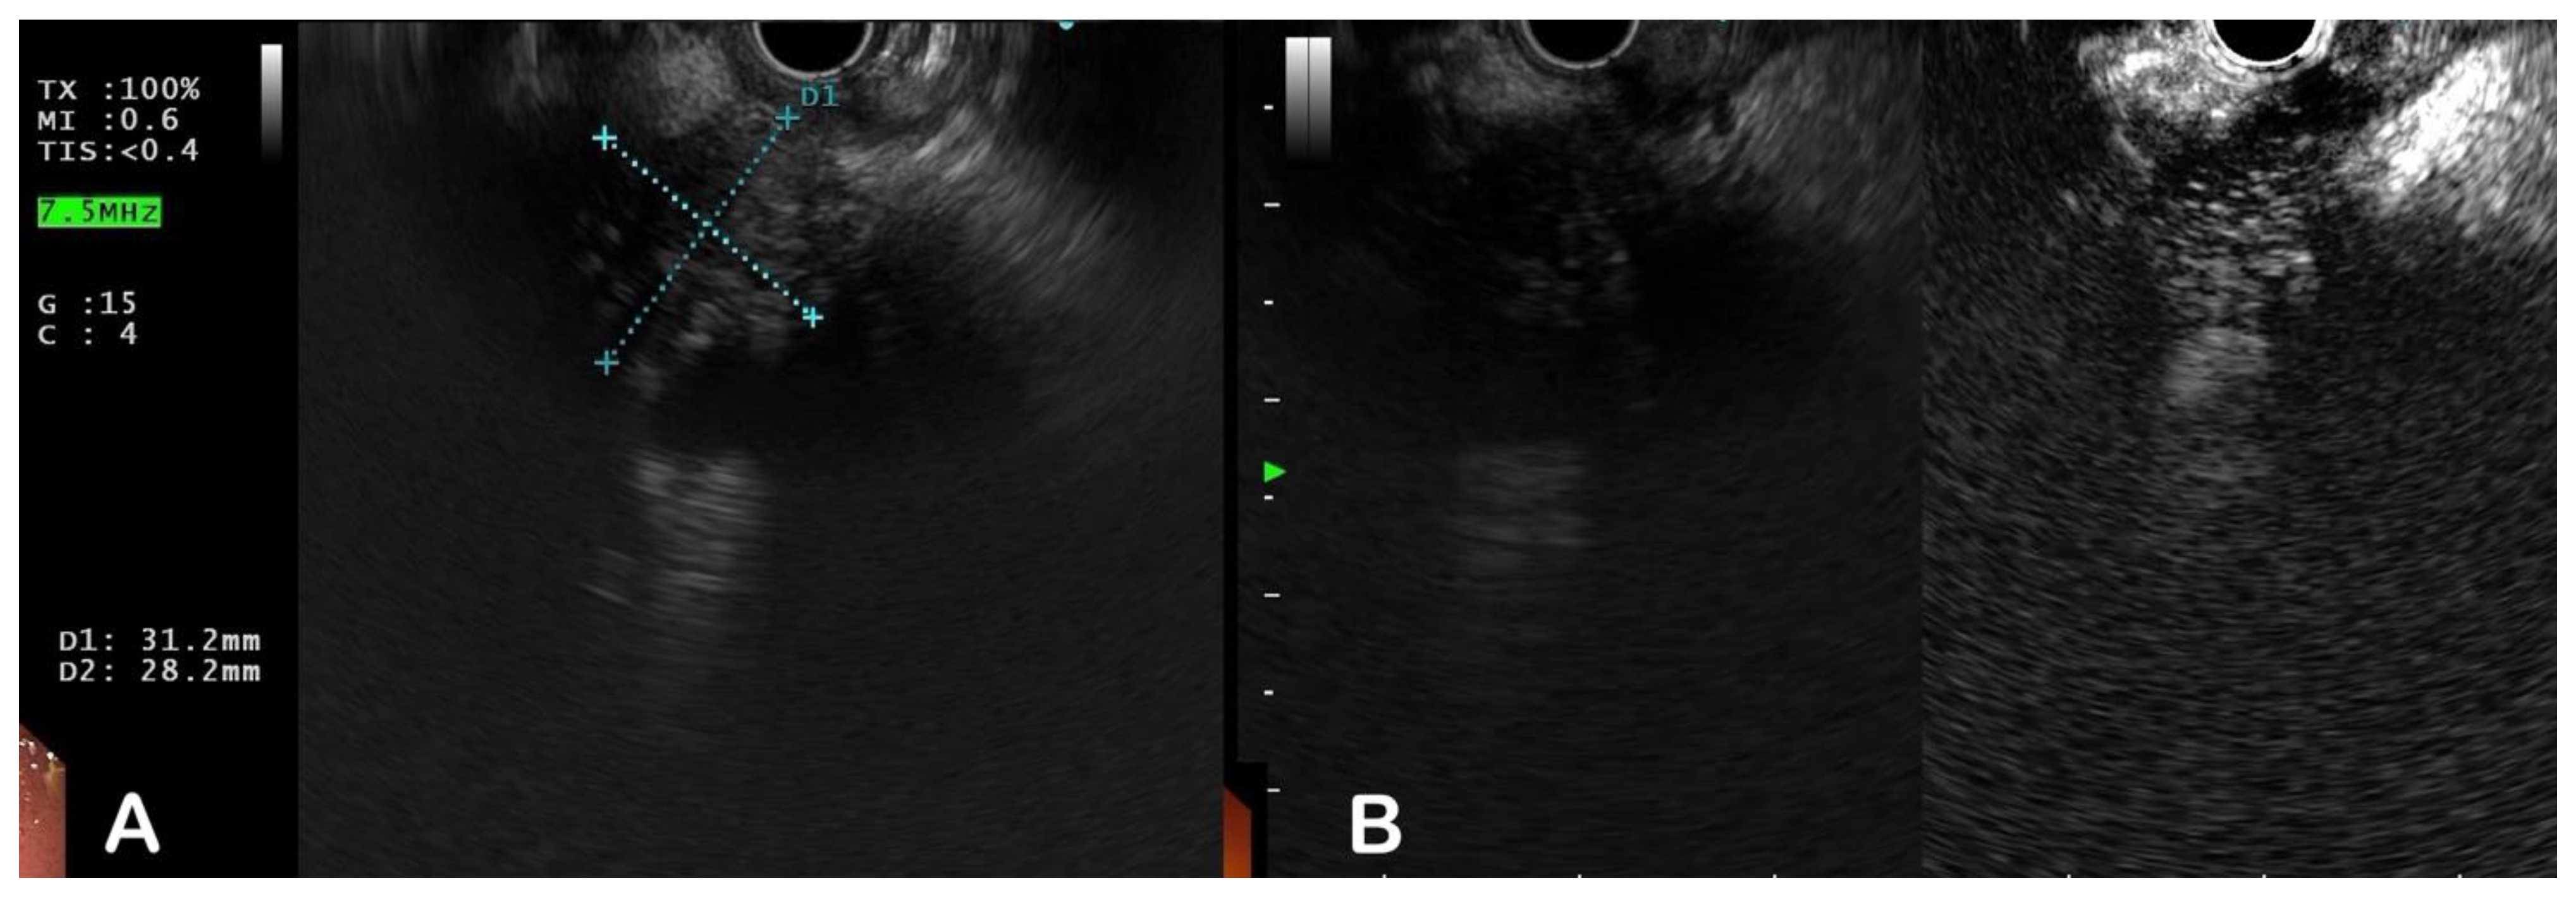

| PDAC is characterised by marked ductal dilatation and parenchymal atrophy. On EUS, a ratio of the diameters of MPD to parenchyma greater than 0.34 strongly suggests malignancy. |